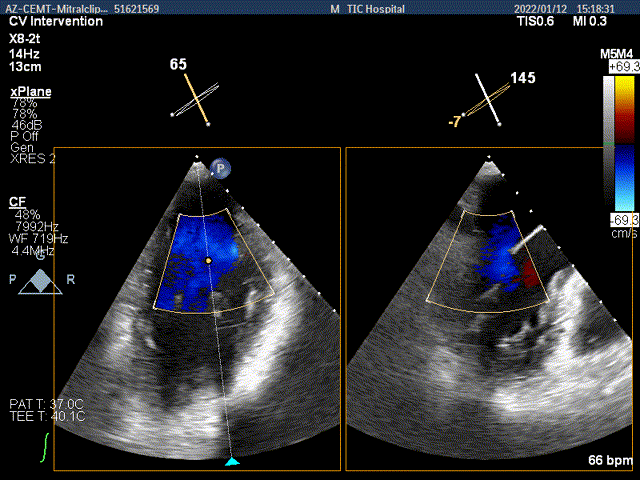

夹子关闭过程中,Color提示内侧1区残余返流

3D-color-VIEW验证残余返流来源

第一个夹子放置侯二尖瓣口平均跨瓣压差:2mmHg

抓捕内侧残余脱垂,color-view示残余返流逐渐减少,主要来源于两个夹子之间

第二个夹子放置侯二尖瓣口平均跨瓣压差:3mmHg